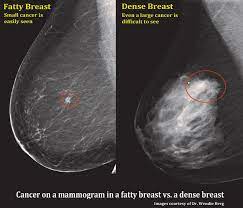

How Does Breast Cancer Look Like On A Mammogram / Mammogram Images Normal Abnormal And Breast Cancer : The outer edges of these cells look fuzzy or spiky (called spiculated).. Healthy mammograms can still vary in appearance. That makes it easy to detect abnormalities, which generally show up as white. If found in an area of rapidly dividing cells or grouped together in a certain way, they may be a sign of dcis or breast. A lump or tumor will show up as a focused white area on a mammogram. Dense breast tissue appears solid.

Mammogram Images Normal And Abnormal from www.verywellhealth.com Any area that does not look like normal tissue is a possible cause for concern. The appearance of normal breast tissue on a mammogram varies from person to person, and no two mammograms look the same. A woman's breast tissue also changes over time, and it is not uncommon for benign lumps, cysts or calcifications to form with age. What does cancer look like on a mammogram? Tumors may be benign or cancerous. Abnormalities such as cancerous tumors usually appear brighter because they are denser. Cancers may be seen as masses (like a ball, but usually with an irregular shape), areas of asymmetry that resemble normal tissue, calcifications (white specks), and/or areas of architectural distortion (imagine the puckering caused by pulling a thread in a piece of fabric). Calcifications are calcium deposits within the breast tissue and they look like small white spots.

Any area that does not look like normal tissue is a possible cause for concern. Invasive breast cancer can appear as a white patch or mass on a mammogram. You may notice dimpling or pitting, and the skin on your breast. A rash isn't the only visual symptom of inflammatory breast cancer. The milk ducts carry your breast milk from lobules, where milk is produced, to your nipple. Magnetic resonance imaging (mri) of the breast — or breast mri — is a test used to detect breast cancer and other abnormalities in the breast. A lump or tumor will show up as a focused white area on a mammogram. 1 the gray areas correspond to normal fatty tissue, while the white areas are normal breast tissue with ducts and lobes. A spiculated breast mass, which has spikes extending out from the main mass, is often highly suggestive of cancer. Macrocalcifications, which look like small white dots on a mammogram. It's so important to listen to the messages our bodies are telling. In addition to mammograms, ultrasound and mri may also be used to take a closer look at changes in the breast. Breast cancer can appear as a spiculated mass, cluster of tiny calcifications, smoothly marginated mass, area of subtle distortion or be invisible on.